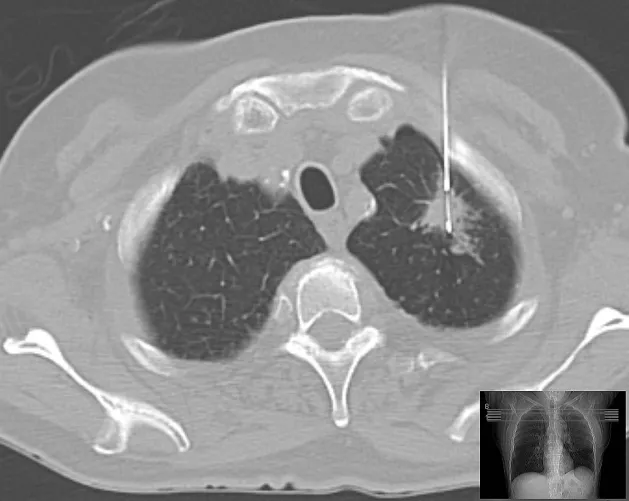

Tüdőbiopszia

CT-vezérelt biposzia tüdő rosszindulatú elváltozásra gyanús képletében. A jobb alsó sarokban a rétegfelvétel magassága látható.